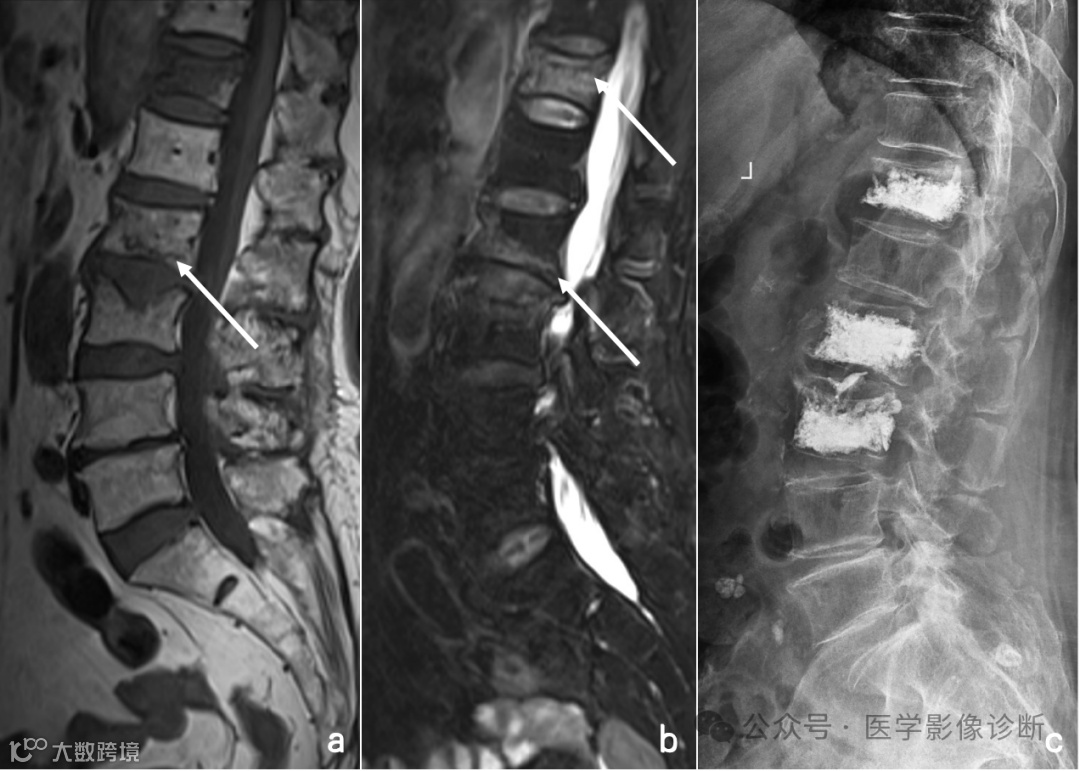

患者,女性,81岁,淋巴瘤化疗后腰痛一周。

腰椎MRI扫描T1WI(A)和T2WI/FS(B)显示多个椎体多发异常信号伴轻度压缩骨折,受恶性肿瘤病史影响放射科医生将其诊断为转移瘤,而遗漏了终版下条带样低信号等良性压缩骨折的征象,患者行椎体活检并成形术后(C),术后病理证实无肿瘤迹象。